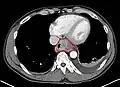

Esophageal cancer as shown by a filling defect during an upper GI series

Although an occlusive tumor may be suspected on a barium swallow or barium meal, the diagnosis is best made with an examination using an endoscope. This involves the passing of a flexible tube with a light and camera down the esophagus and examining the wall, and is called an esophagogastroduodenoscopy. Biopsies taken of suspicious lesions are then examined histologically for signs of malignancy.

Additional testing is needed to assess how much the cancer has spread (see #Staging, below). Computed tomography (CT) of the chest, abdomen and pelvis can evaluate whether the cancer has spread to adjacent tissues or distant organs (especially liver and lymph nodes). The sensitivity of a CT scan is limited by its ability to detect masses (e.g. enlarged lymph nodes or involved organs) generally larger than 1 cm.[41][42] Positron emission tomography is also used to estimate the extent of the disease and is regarded as more precise than CT alone.[43] Esophageal endoscopic ultrasound can provide staging information regarding the level of tumor invasion, and possible spread to regional lymph nodes.